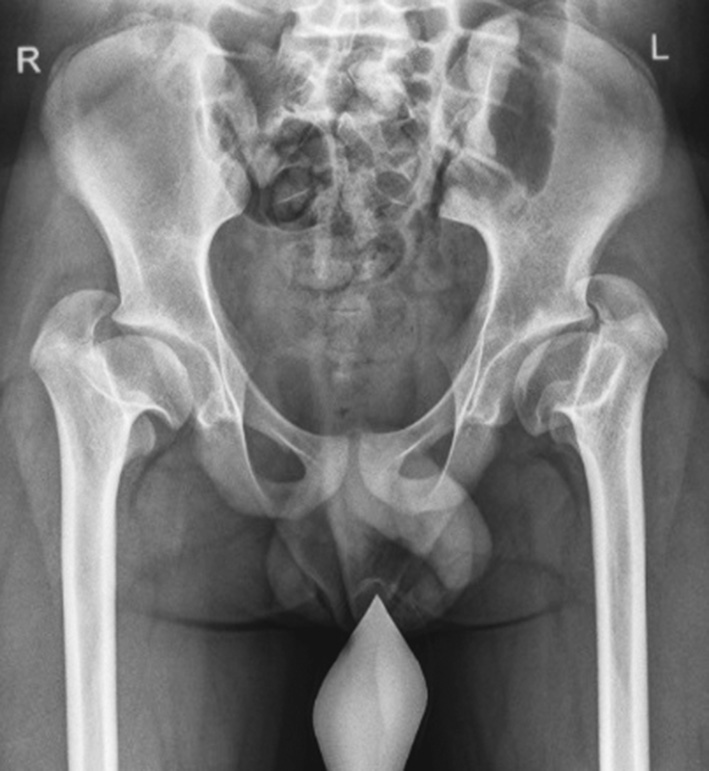

In all 350 patients observed, the ratio of the greater trochanter apex to the center of the femoral head was in the pathological range, which served as the main criterion for inclusion in the study. For a detailed analysis of the ongoing anatomical changes, we studied additional indicators characterizing the ratio of the femoral head and the greater trochanter in the frontal view in 56 examined patients (112 hip joints). The development of 48 (42.9%) joints in them was normal (with unilateral lesion) (Fig. 1).

Fig. 1. Indicators characterizing the ratio of the femoral head and the greater trochanter in the frontal view (Mccarthy J.J., Weiner D.S., 2008, as amended) [12]. ATD — articulotrochanteric distance; LTA — lesser trochanter-to-articular surface distance; TTD — trochanter-to-trochanter distance